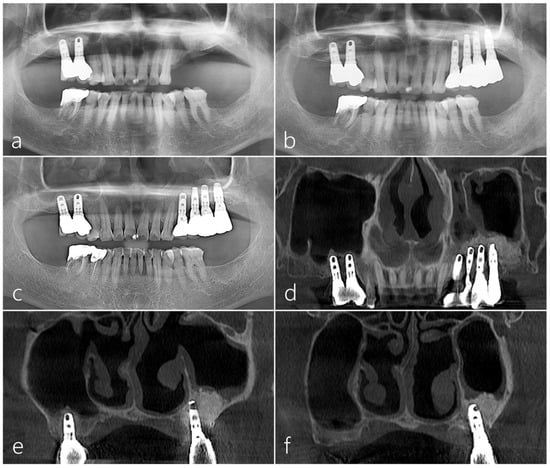

2.2. Case 2

2.3. Case 3